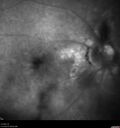

Most viewed - Optic nerve (disc) drusen and choroidal neovascular membrane 85 year old man - The left eye has had poor vision for 7-8 years. The right eye is OK. He was in for a checkup and his ophthalmologist noticed a problem and asked him to see retina doctor. Â

Medical Hx: Cancer.

Surgical Hx: Back Surgery. Gallbladder. Appendectomy. Colon Cancer.

Systemic Meds: Propafenone Hydrochloride, 225 mg oral tablet. Rosuvastatin. PAROXETINE HCL. GABAPENTIN. DONEPEZIL. Asp

VA OD: Dcc20/25-2 OS: DccCF 1ft

IOP: TP: OD:13 OS:12

Patient's right eye was treated with Avastin and was dry with one shot.